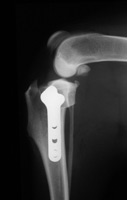

• cement-less Total Hip Joint Replacement

(please click on photos to enlarge)